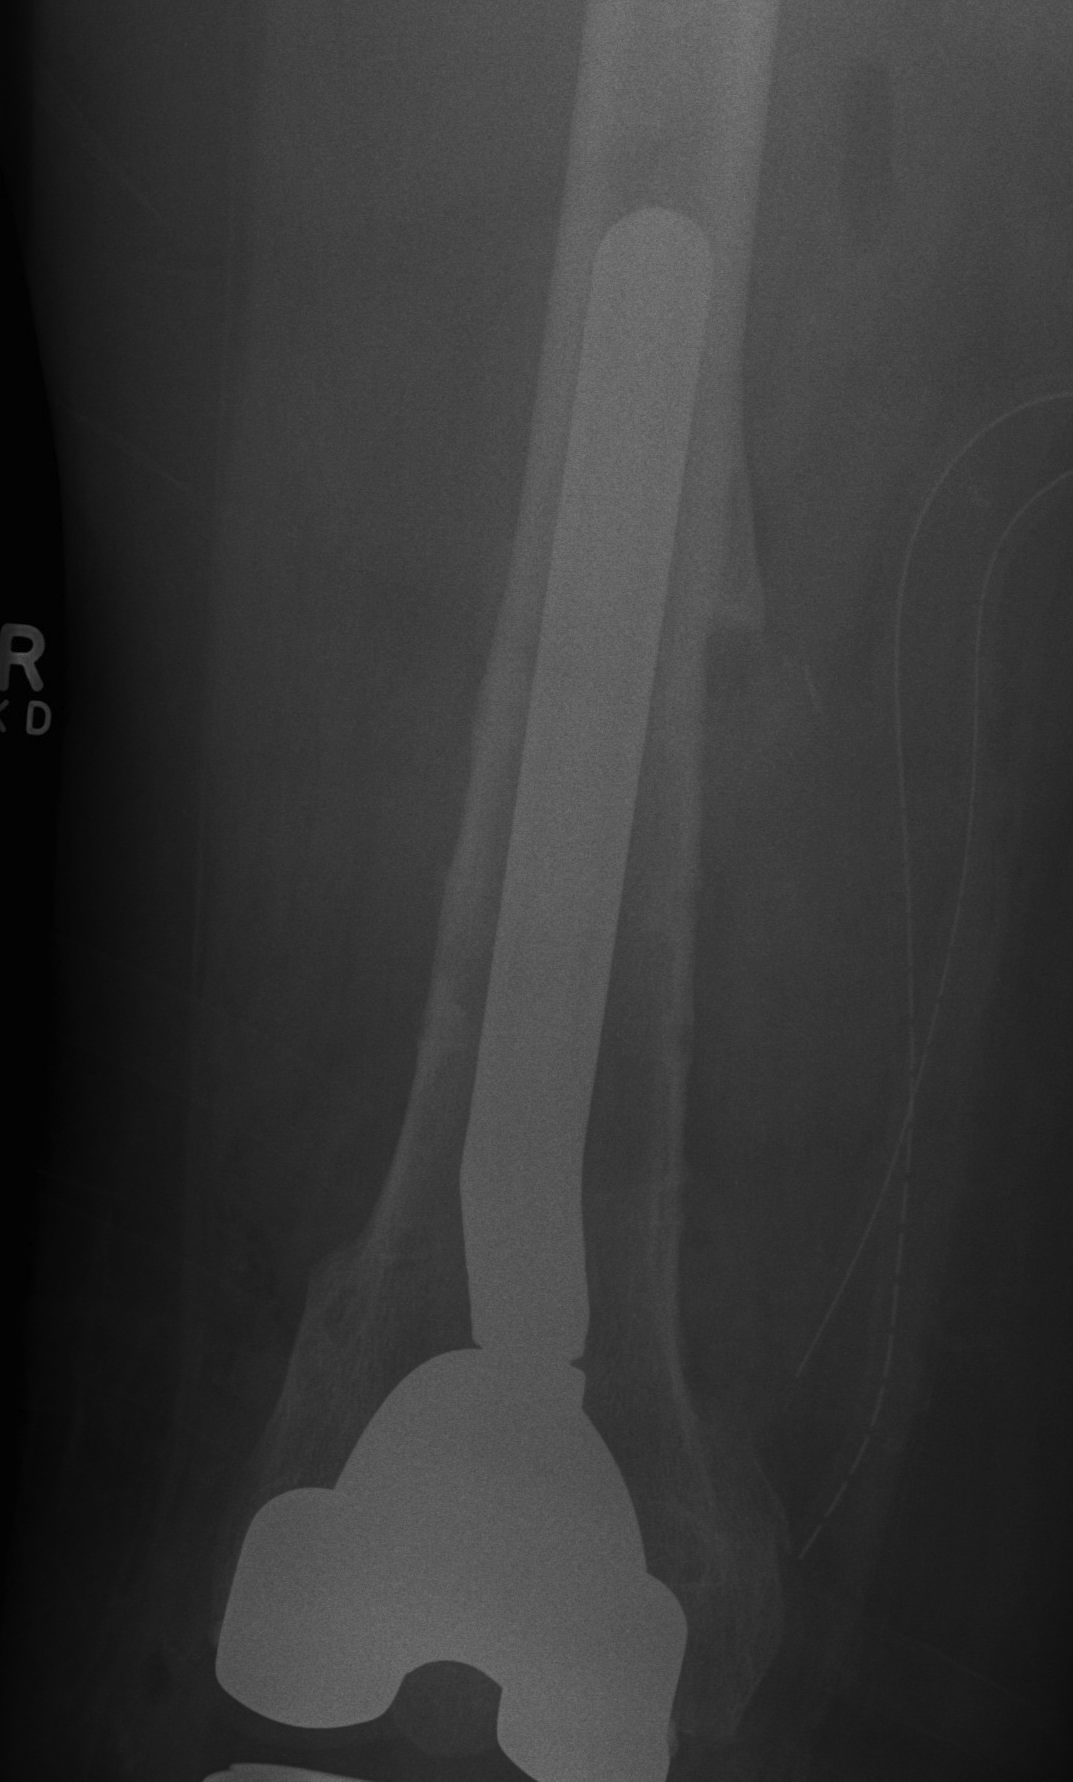

Initial press fit

- implant geometry fits the cortical bone in the proximal femur

- good initial mechanical stability

Biological fixation for success

- good press fit

- minimal micromotion

- bony or fibrous tissue ingrowth or ongrowth